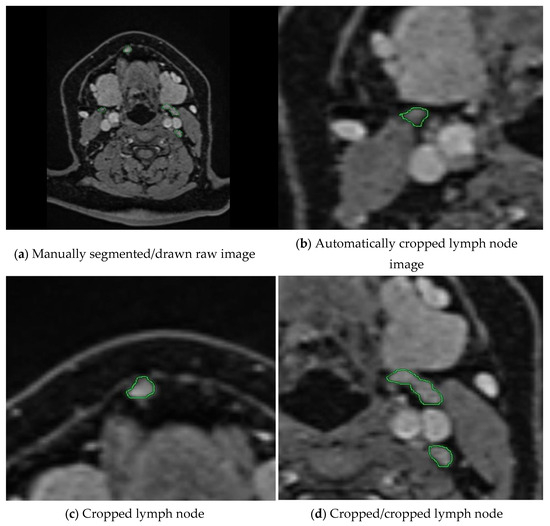

In the next step, we calculate the rectangles called bboxes that surround the boundaries of closed geometric shapes in the binary images. After determining the number of these rectangles, i.e., the number of regions drawn with a green line, the loop is started. From this point onward, we verify two conditions. In this process, it expands the perimeter of the bbox by expanding the Expansion Border Value. In this study, we chose the threshold value as 150 pixels for the dataset we have. Thus, we perform cropping by expanding 300 pixels on each axis. The second condition is whether the currently controlled bbox is included in another bbox up to the proximity threshold value. If these regions are within 150 pixels of each other, which is the specified threshold value, this lymph node passes this region as cropped. If not, it will perform cropping at the expansion border value. This control mechanism, as shown in the example in Figure 2, controls the cropped areas and prevents repeated cropping of the same lymph node.

Figure 2. The workflow of our preprocessing program for semi-automatic segmentation is illustrated. (a) A raw medical image where lymph nodes have been manually annotated by an expert using green markings. (bd) show the cropped images obtained by our proposed method, which automatically extracts the annotated regions. Our program crops each lymph node marked by the expert and ensures that the same lymph node is not cropped more than once through a control mechanism. This prevents redundant processing and ensures that each lymph node is included only once in the dataset.